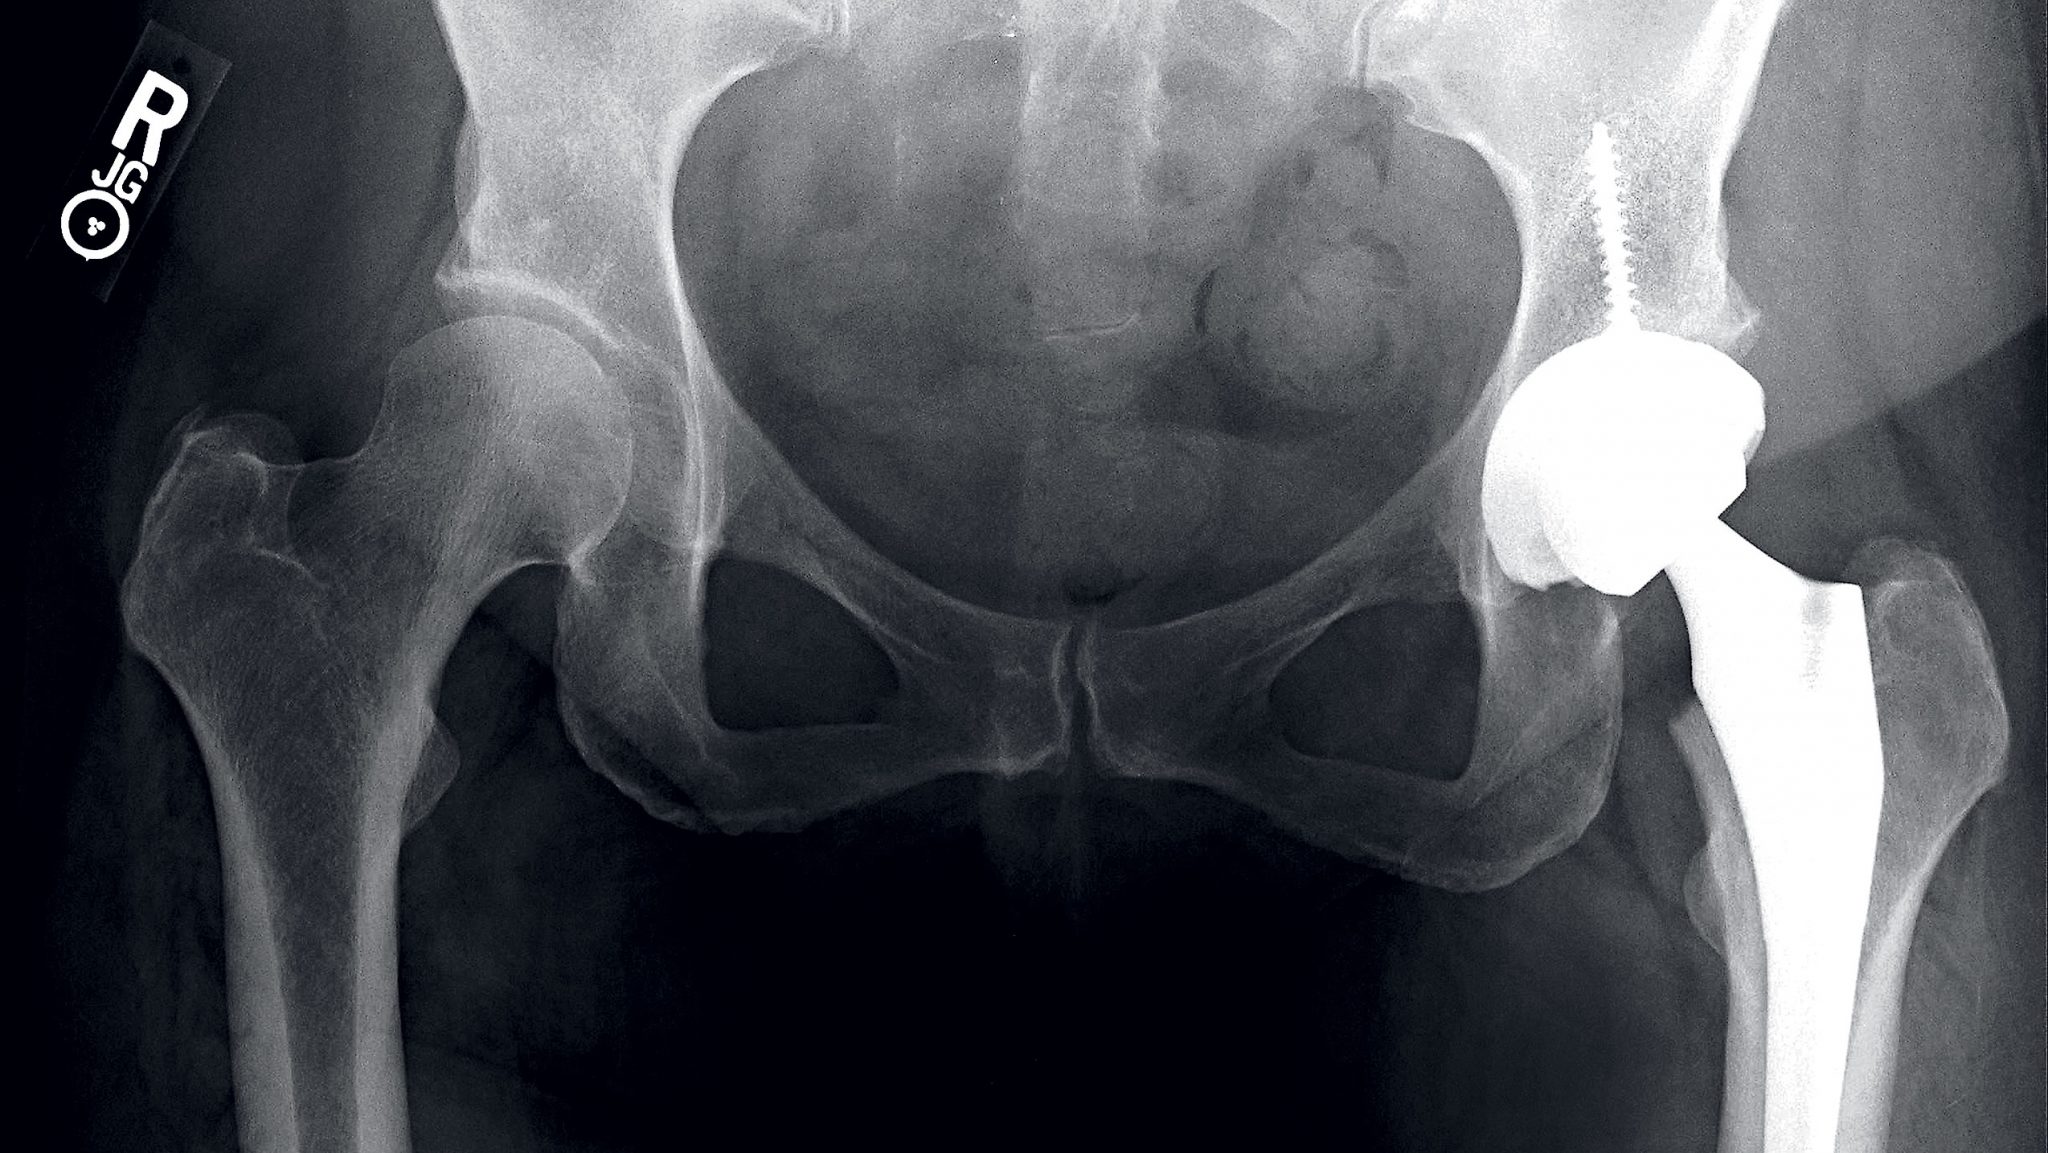

From 1993 to 2009, the number of Americans undergoing total hip replacement has more than doubled, while total knee replacements have tripled, according to a study by the Journal of Bone and Joint Surgery. Researchers anticipate that by 2030 the number of surgeries for ages 45 to 54 could increase six-fold for total hip replacements and as much as 17-fold for knee replacements.

At 41, after the birth of her second daughter and unable to walk far without pain, Keaney underwent a total hip replacement.

Scott Faucett, a DC orthopedic surgeon specializing in knee and hip replacement and preservation, says that participating in sports can wear down joint cartilage before its time—a condition known as osteoarthritis—resulting in pain and joint damage.

Improvements in implant technology over the past decade also explain the dramatic rise in surgeries. Manufacturers have developed what Faucett calls “revolutionary plastics,” with wear rates about one-tenth of those used in implants 10 or 15 years ago. Both Faucett and Goyal say the new implants are expected to last more than 30 years, at least a decade longer than older ones. This, combined with improvements in surgery—now less invasive, less risky, and with reduced recovery times—has made doctors and patients more willing to consider replacement at an early age.